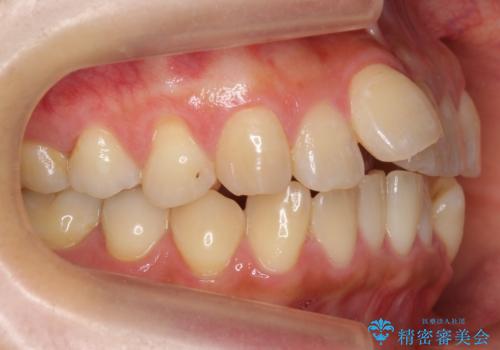

20代女性 出っ歯 ガミースマイルを改善

- 出っ歯を主訴に来院。

途中、前歯にマイクロインプラントを使用し過蓋咬合の改善も兼ねて、ガミースマイルの改善も行いました。

前歯の叢生がきつく、また、過蓋咬合のため治療に時間がかかりましたが、きれいに治しました。

ガミースマイルの改善もお任せください。